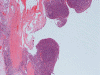

Histopathology: The lesion is encapulated cystic structure with the wall lined by nodules of lymphoid tissue (Panel A  and B) that are devoid of any evidence of hematopoiecic malignancy. Within this lymphoid tissue are small pink islands (Arrow in Panel C) and on higher magnification (Panel D) these islands are squamous cell nests. These islands are Hassell corpuscles and the lymphoid tissue is in fact thymic tissue. The cyst appears to have sustained repeated hemorrages. Both recent hemorrhage (Panel E) and cholesterol clefts consistent with resolved hemorrhage (Panel F) are present.

Cervical thymic cysts can vary in size up to few centimeters, may be unilocular or multilocular. The lateral location is a good clue to support the diagnosis. The cyst contents vary from clear serous fluid to hemorrhagic or purulent fluid. They may contain semi-solid, gelatinous, necrotic debris, blood or cholesterol crystals (like this case). Thymic parenchyma, lymphoid tissue and Hassall’s corpuscles found within the cyst wall are considered pathognomic findings. The cyst wall may be devoid of epithelial lining or may have cuboidal, stratified or ciliated epithelium. Identification of the Hassall’s corpuscles is the key to correct diagnosis and sometimes they may not be abundant. Secondary changes due to hemorrhage are also common findings. Sometimes, pressure necrosis may lead to granulation tissue. No ectopic thyroid tissue should be present. The diagnosis is usually straight forward.